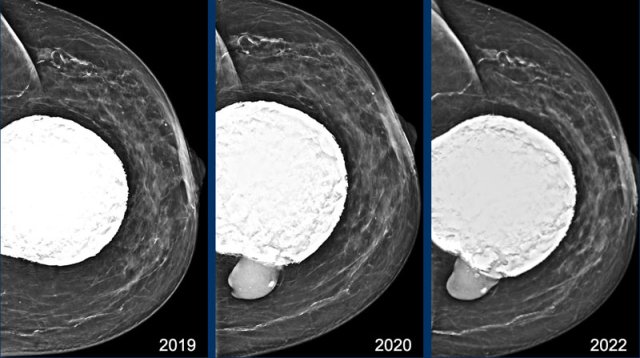

In 2019 the mammogram shows extensive capsular calcifications and a very round shape of the breast implant.

This indicates a contracture of the implant.

At follow up in 2020 the contour has changed and now there is silicone beyond the capsule, which is a definitive sign of extracapsular rupture (arrow).

This elderly patient did not not want surgery, but only wanted screening for possible malignancy.

In 2022 at follow up exam not much has changed. Modern Silicone gel is more cohesive and has less tendency to spread.